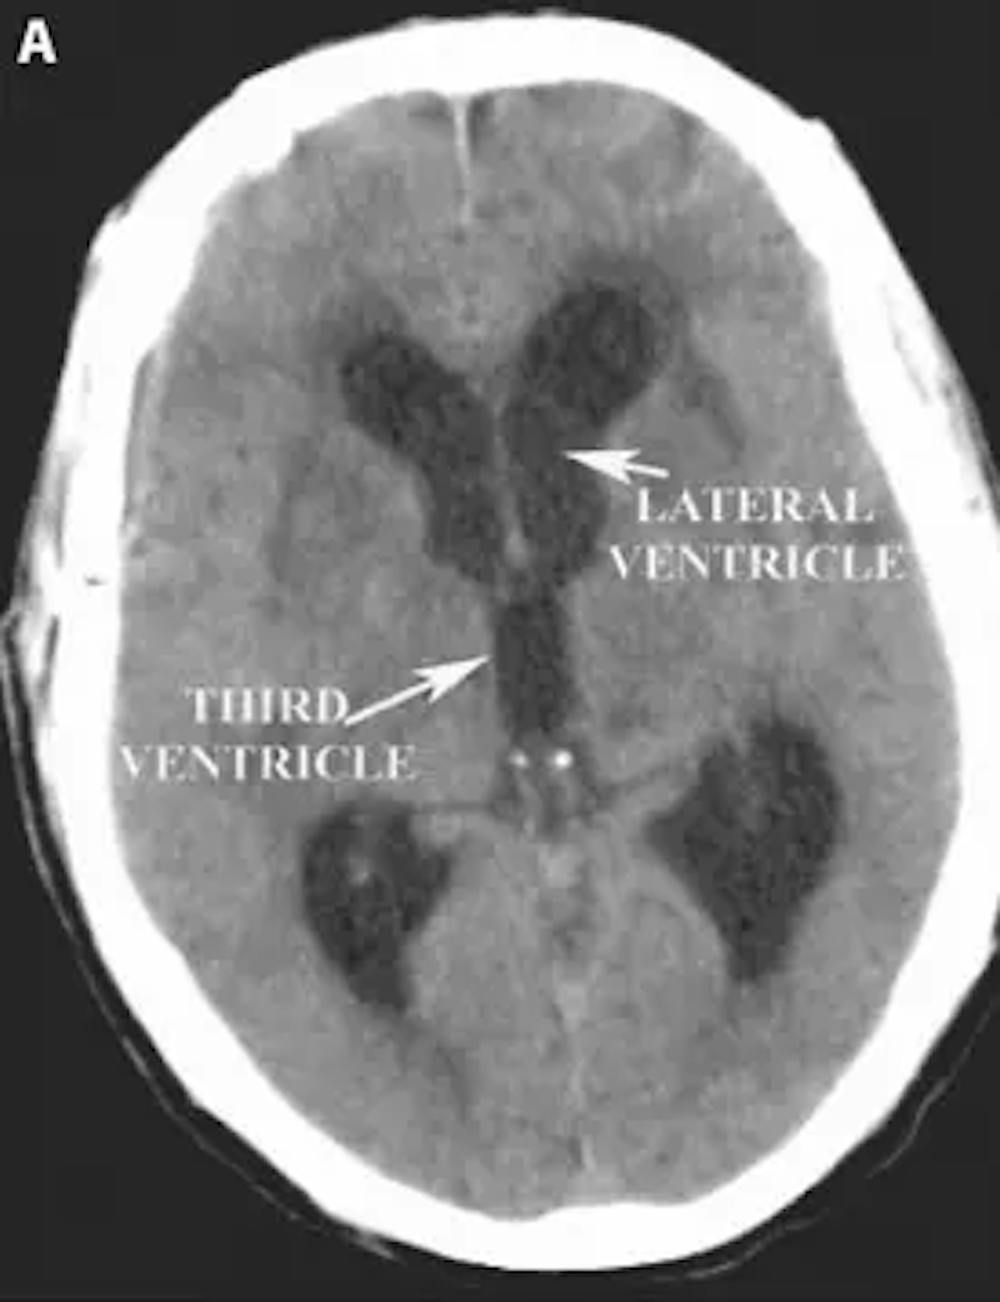

أ) التصوير المقطعي المحوسب للرأس المحوري قبل الجراحة يوضح تضخم البطينين.